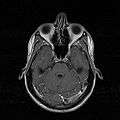

MRI image showing nasal septum.

MRI image showing deviated septum